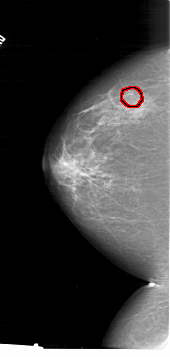

FILE: A_1415_1.LEFT_MLO.OVERLAY

TOTAL_ABNORMALITIES 1

ABNORMALITY 1

LESION_TYPE CALCIFICATION TYPE PLEOMORPHIC DISTRIBUTION CLUSTERED

ASSESSMENT 4

SUBTLETY 3

PATHOLOGY MALIGNANT

TOTAL_OUTLINES 1

BOUNDARY